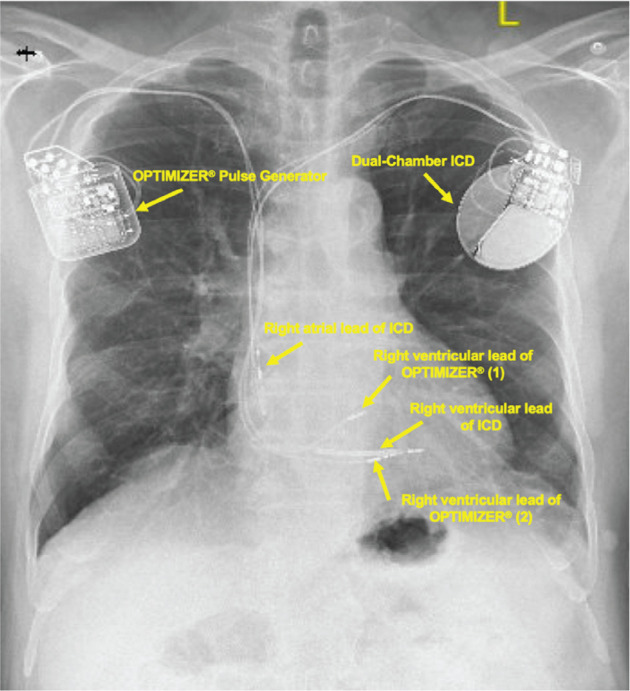

We present a case report of a patient undergoing implantation of a cardiac contractility modulation (CCM) device. The Optimizer® Smart Implantable Pulse Generator (Impulse Dynamics, Orangeburg, NY, USA) provides electrical energy to the right ventricular septum to modulate cardiac contractility and improve cardiac function in heart failure patients. The non-excitatory electrical signals are delivered by transvenous leads during the refractory period. Anesthetic administration during implantation can affect appropriate lead positioning. Propofol at high doses can attenuate diaphragmatic contraction and discomfort from inappropriate lead positioning, resulting in diaphragm stimulation. Therefore, local or conscious sedation is preferred during CCM device implantation. In patients undergoing procedures with this CCM device in situ, the Optimizer® activity causes upward deflections of the RS segment on the electrocardiogram. Also, strong electromagnetic fields can disrupt device function. This case report reviews the novel CCM device and its major anesthetic considerations.